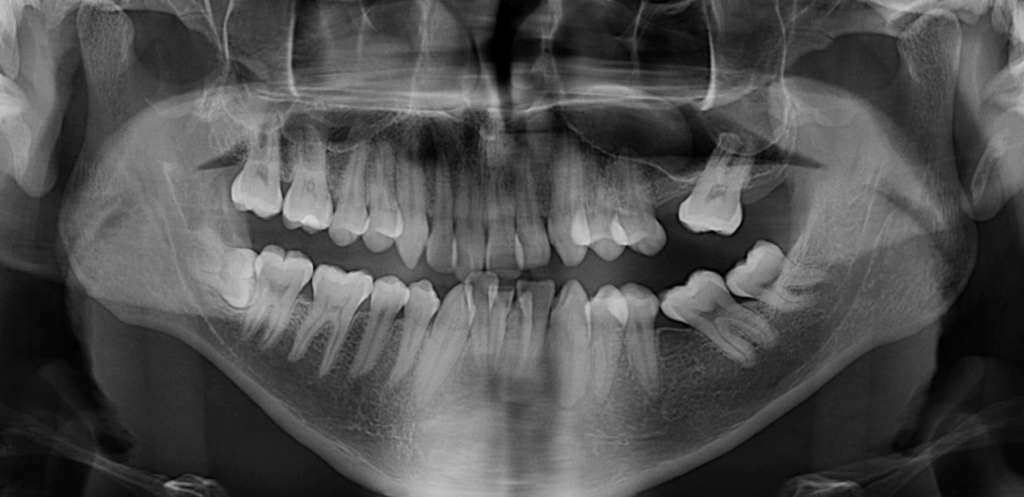

Radiografia Panorámica

caso 344 - radiografia panoramica 01 IDM

A la evaluación de la radiografía panorámica se observa aplanamiento del contorno condilar bilateral, neumatización de ambos senos maxilares, la presencia de un quiste de retención mucoso en el seno maxilar izquierdo, asimismo también se observa apiñamiento dental, presencia de placa cervical mineralizada y la pieza 48 impactada hacia mesial.